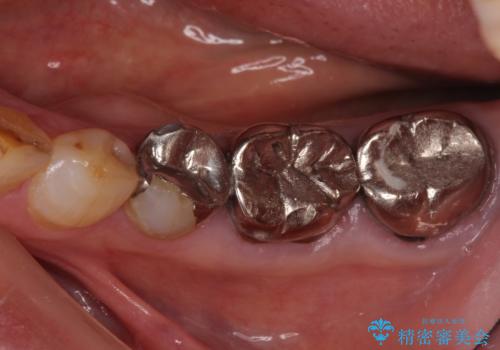

全ての奥歯の銀歯をセラミックに メタルフリー治療

- 奥歯に装着されている銀歯を全て外したいとのことで来院された患者様です。

土台に含まれている金属も含め、奥歯の金属は全て除去し、オールセラミッククラウンやセラミックインレーにて治療することとしました。